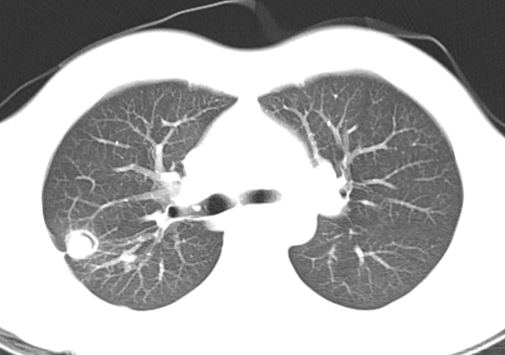

3. 继发性肺结核:继发性肺结核胸部影像表现多样。轻者主要表现为斑片、结节及索条影,或表现为结核瘤或孤立空洞;重者可表现为大叶性浸润、干酪性肺炎、多发空洞形成和支气管播散形成树芽征等;反复迁延进展者可出现肺损毁,损毁肺组织体积缩小,其内多发纤维厚壁空洞、继发性支气管扩张,或伴有多发钙化等,邻近肺门和纵隔结构牵拉移位,胸廓塌陷,胸膜增厚粘连,其他肺组织出现代偿性肺气肿和新旧不一的支气管播散病灶等。

*典型继发性肺结核:右上肺病变(上肺尖后段及下叶背段为结核好发部位),近心端空洞,可见引流支气管,周围可见播散灶(卫星灶)

*双上肺为主的多发空洞,痰抗酸染色阳性,实为非结核分枝杆菌肺病(胞内分枝杆菌肺病),误诊为肺结核

*典型右下叶背段沿支气管播散的树芽征,确诊为肺结核(但仍然需与其他支原体肺炎以及非结核分枝杆菌肺病鉴别)

*左上肺病变,具有多态性多灶性,误诊为肺结核,实为支原体肺炎(树雾征)

*表现为「反晕征」的肺结核,既往反晕征常描述为机化性肺炎、血管炎等特征性影像学表现,目前在肺结核中不少见。

*临床中尘肺误诊为肺结核非常常见,对于弥漫性病变一定强调职业史的询问

*空气新月征常作为曲霉菌特征性影像学表现,但肺结核也可以表现。此例患者为肺结核。